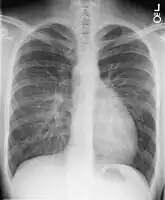

Chest X-ray: On chest X-ray (CXR), transposition of the great vessels typically shows a cardio-mediastinal silhouette appearing as an "egg on a string ", in which the enlarged heart represents an egg on its side and the narrowed, atrophic thymus of the superior mediastinum represents the string.[9]

X-ray showing characteristic finding in case of transposition of the great vessels which is called egg on side sign -